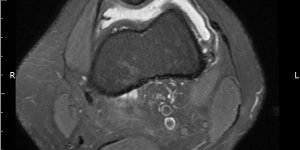

Monoarthropathy – Knee | Cases

Published on Jan 12, 2021

27 female 10 Year history of Knee pain. Used to do running but now doesn’t due to pain. Previous diagnosis – Bakers Cyst which was drained. Examination No effusion Full ROM, no pain with overpressure NAD ligaments NAD meniscal test (McMurrays) Cyst present in Popliteal fossa over gastrocnemius region. Non tender MRI requested to ascertain cause [...] Read more